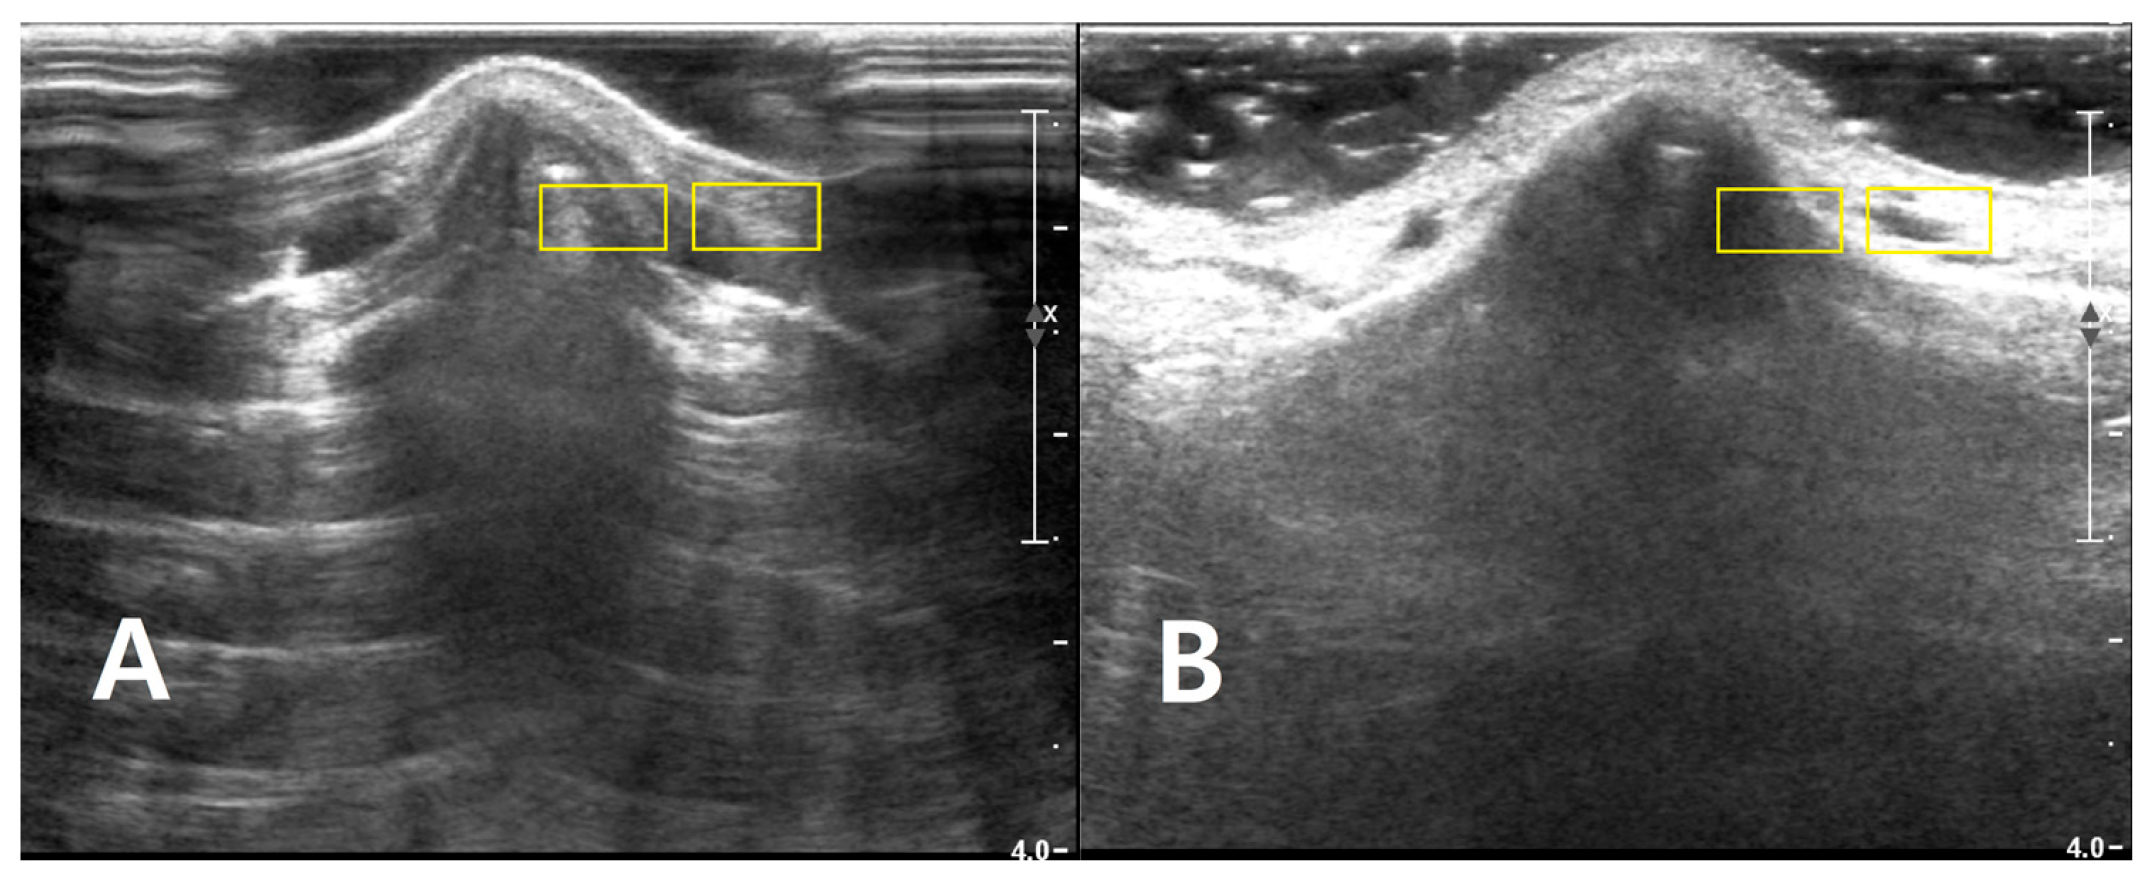

Two rectangular ROIs were defined at a fixed depth and orientation on the PAD image and then reapplied to the LGB image with only minor adjustments to maintain alignment: Cortical ROI (ROI_bone): A small rectangle (approximately 6 × 3 mm) confined to the bright cortical band at the nasal dorsum, avoiding saturated pixels (intensity = 255) and excluding overlying reverberation or shadowing. Adjacent soft-tissue ROI (ROI_soft): A rectangle of similar size placed 1–2 mm lateral to the cortical ROI at the same depth, sampling homogeneous soft tissue (Figure 2). The exact lateral position of the ROIs was adjusted so that, in both PAD and LGB images, ROI_bone and ROI_soft remained aligned to the same anatomical level (depth mismatch ≤ 0.5 mm; angular mismatch ≤ 5°). For subjects with cine data, the same ROIs were propagated across five consecutive frames: the frame with the highest mean intensity within ROI_bone and its two preceding and two subsequent frames. For each frame, the mean (μ) and standard deviation (σ) of the 8-bit gray-level values were recorded for ROI_bone and ROI_soft. For subjects with only static images available, ROI_bone and ROI_soft were repositioned across three to five adjacent locations along the same cortical segment, and measurements were averaged (Figure 3).

Figure 2. Longitudinal B-mode ultrasound images of the nasal dorsum in a volunteer illustrating ROI placement for quantitative analysis of each (A) PAD and (B) LGB image. Two rectangular ROIs (approximately 6 × 3 mm, yellow boxes) are drawn at the same depth. The image of cortical ROI was confined to the bright nasal cortical line, avoiding saturated pixels and obvious artifacts, and the adjacent soft-tissue ROI is positioned 1–2 mm lateral at the same depth to sample homogeneous soft tissue for CNR and SNR calculations. The images are provided for illustrative purposes to demonstrate ROI placement and were acquired.